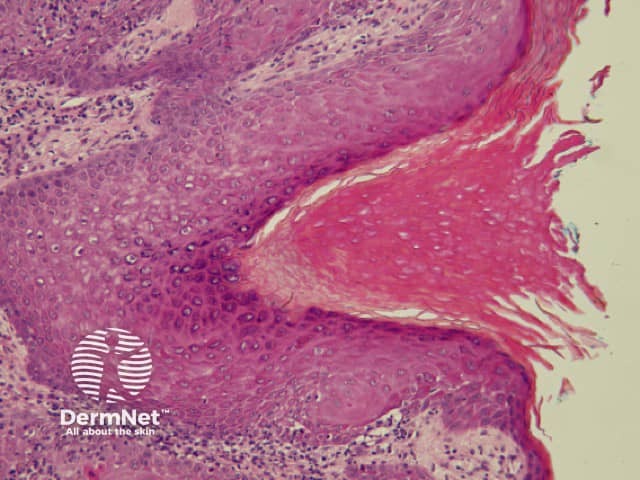

Curved lines

Curved lines are seen in dermatoscopy of pigmented keratinocytic proliferations that are either acanthotic, such as seborrhoeic keratosis, or in specific locations, such as close to mucocutaneous junctions, as with some labial and genital melanotic macules.

The dermatoscopic features of melanotic macules vary with site reflecting the differences in the anatomy of the dermoepidermal junction in normal skin (ink spot lentigo, Figures 6a, 6b) and mucocutaneous transition zones (Figures 7a and 7b). The histology is, however, reasonably similar irrespective of site (Figure 8).